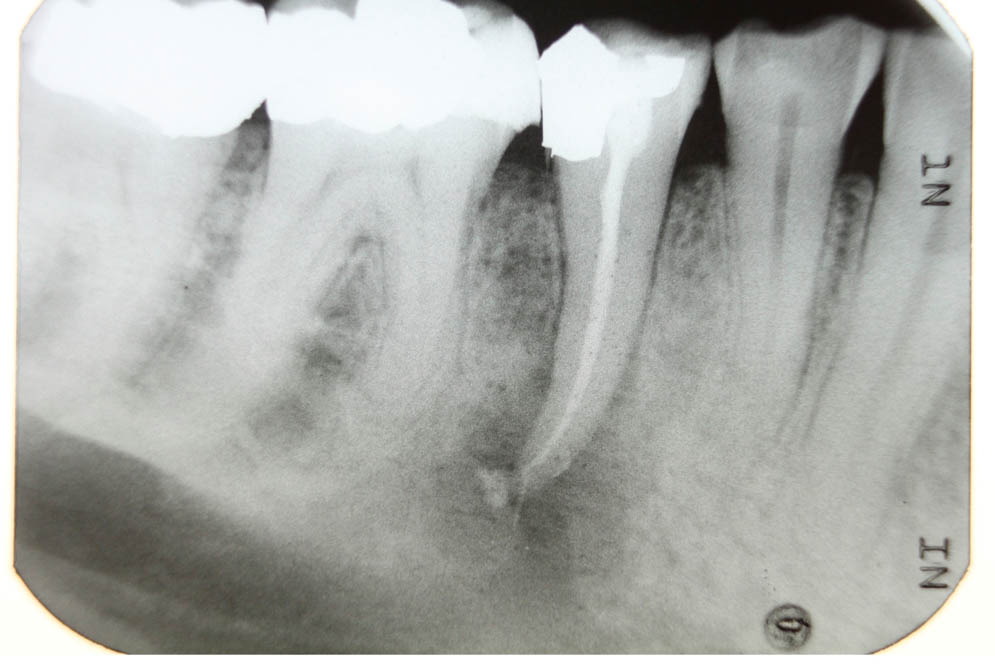

Die dreidimensionale Bildgebung entsteht durch den Einsatz modernster Technologie. Röntgenrohre mit gegenüberliegendem Bildsensor bewegen sich kreisförmig um den Kopf des Patienten und erstellen dabei zahlreiche Einzelaufnahmen. Diese Bilddaten werden digital zu einem detailreichen, dreidimensionalen Gesamtbild zusammengefasst. Sie liefern eine präzise Darstellung von Zähnen, Nerven, Knochen- und Gewebestrukturen. Damit bilden sie eine sehr exakte und aussagekräftige Grundlage für Diagnostik und Behandlungsplanung. Die beiden Abbildungen verdeutlichen den Unterschied zwischen herkömmlichen Röntgenbildern und der digitalen Volumentomographie (DVT): Während Abbildung 1 die anatomischen Strukturen des Mundraums lediglich zweidimensional zeigt, bietet Abbildung 2 eine dreidimensionale und detailliertere Darstellung von Zähnen und Kiefer.